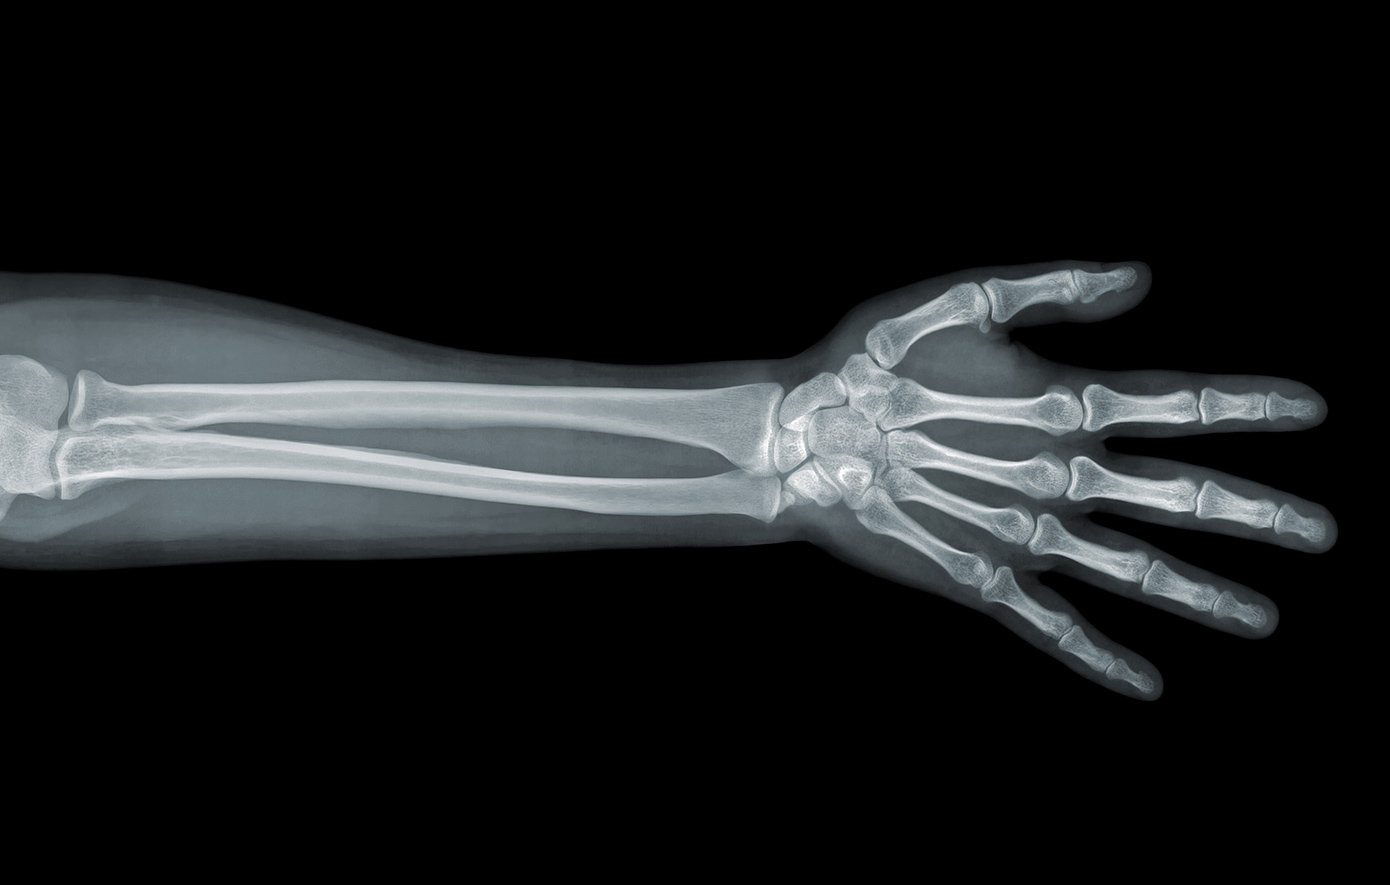

Ως παράδειγμα έφερε την περίπτωση ενός ασθενή με κάταγμα στον καρπό, στον οποίο δοκιμάστηκε το «Bone-02». Υπό κανονικές συνθήκες, θα χρειαζόταν χειρουργική επέμβαση για την τοποθέτηση μεταλλικής πλάκας και βιδών, οι οποίες θα έπρεπε να αφαιρεθούν με δεύτερη χειρουργική επέμβαση τον επόμενο χρόνο.

Εντούτοις, με μόνο μια ένεση, το κάταγμα θεραπεύτηκε μέσα σε τρία λεπτά, ανέφερε ο Xianfeng.